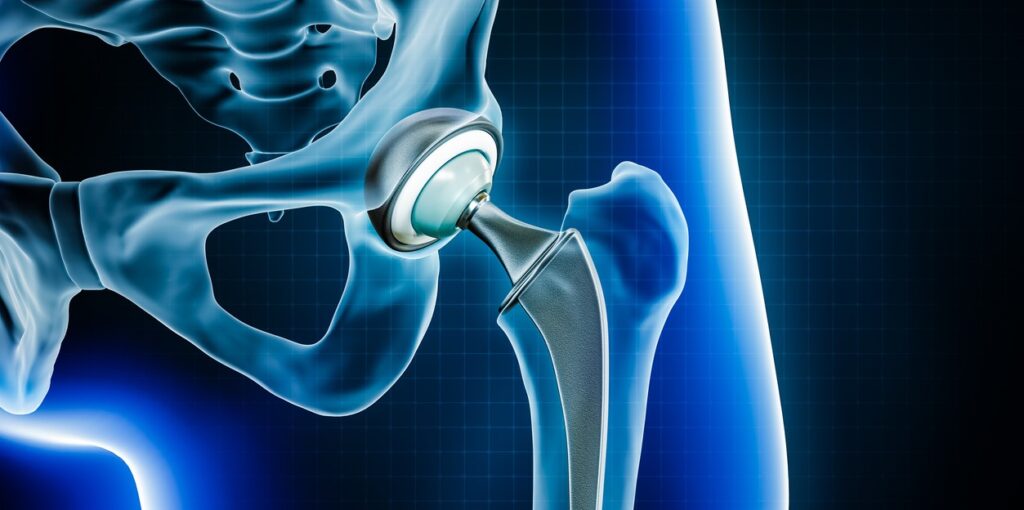

Hip replacement involves removing the damaged parts of the hip joint and replacing them with artificial components made of metal, ceramic, or high-grade plastic. The goal of the surgery is to reduce pain, improve joint function, and enhance mobility. There are two main types of hip replacement:

1.Total Hip Replacement (THR): The entire hip joint (femoral head and socket) is replaced.

2.Partial Hip Replacement: Only the femoral head is replaced, often used for certain types of fractures.

Hip replacements can also be done using cemented or uncemented implants, depending on the patient’s age, bone quality, and activity level. Orthopedic & Joint Replacement Treatment in India.